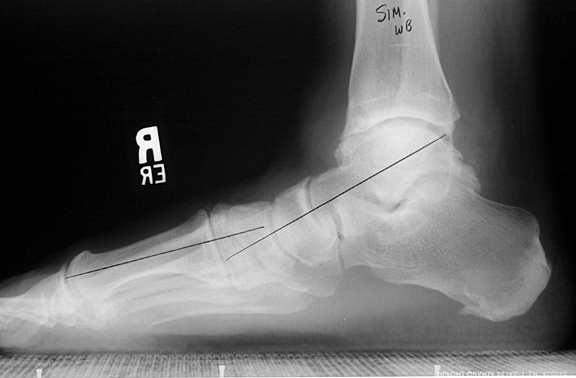

See more ideas about ankle fracture, sprained ankle, radiography. Affordable and search from millions of royalty free images, photos and vectors. Study xray anatomy using smart web & mobile flashcards created by top students, teachers, and professors. Metatarsal fracture, metatarsal stress fracture, lisfranc injury, jones fracture